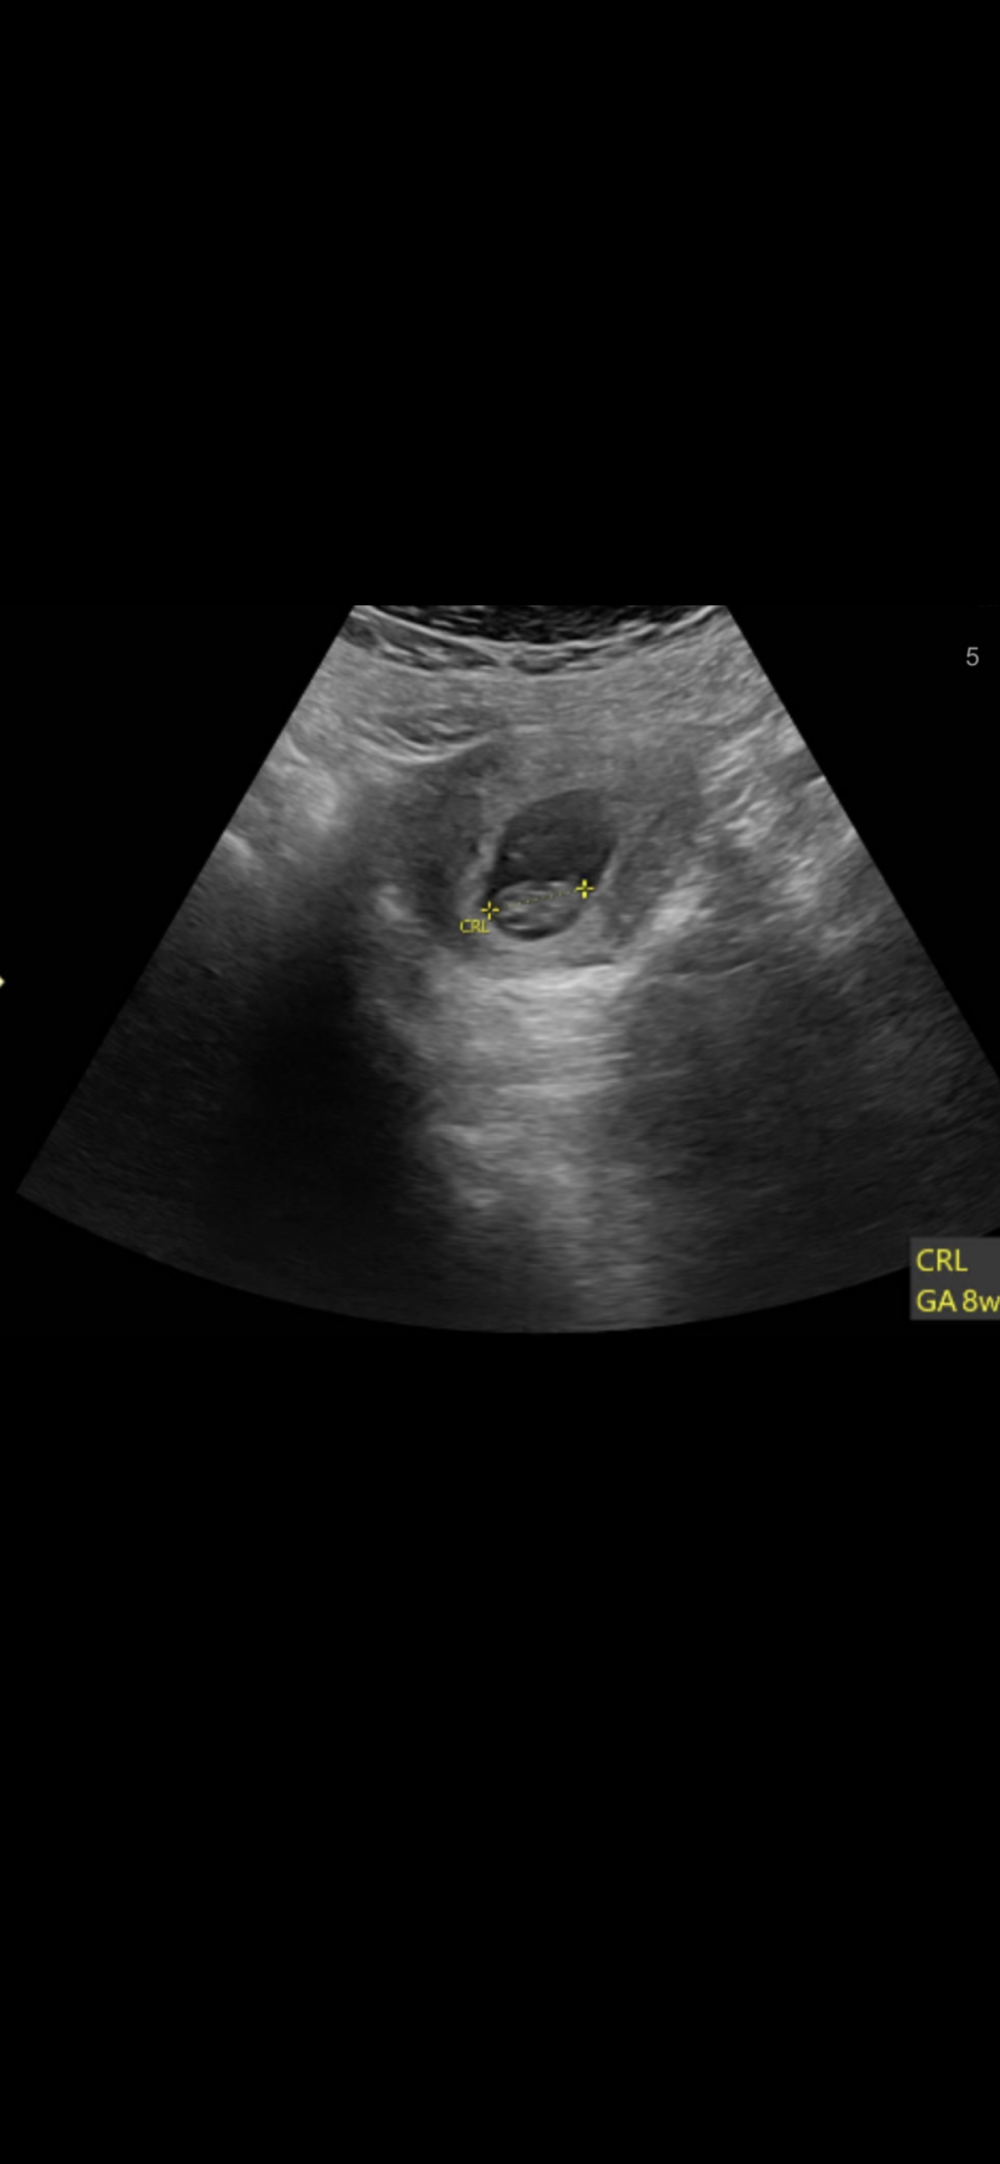

مافيني صبرر رحت انبش🏃🏻‍♀️🏃🏻‍♀️🏃🏻‍♀️

توقعاتكم اصحاب الخبرة 🦦